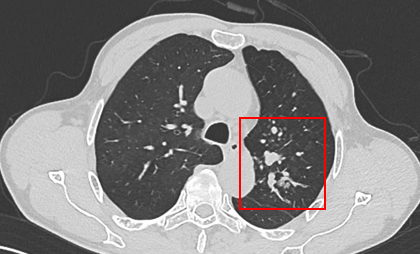

PET-CT(2023年9月):右下肺叶发现6.9×6.7×6.6cm的FDG高摄取肿块,伴右侧第7、8肋骨侵犯可疑,右肺门淋巴结肿大,双肺上叶多发结节,考虑腺癌谱系疾病。

CT及PET-CT随访(2023年11月、2024年1月):评估新辅助治疗效果,右下肺叶肿块缩小,右肺门淋巴结代谢活性消失,右肺上叶结节稳定但代谢活性降低,左肺上叶及双侧磨玻璃样病变稳定。

新辅助治疗:患者接受4周期新辅助化疗联合免疫治疗(培美曲塞、顺铂、纳武利尤单抗),治疗后影像学显示肿块缩小,代谢活性降低。